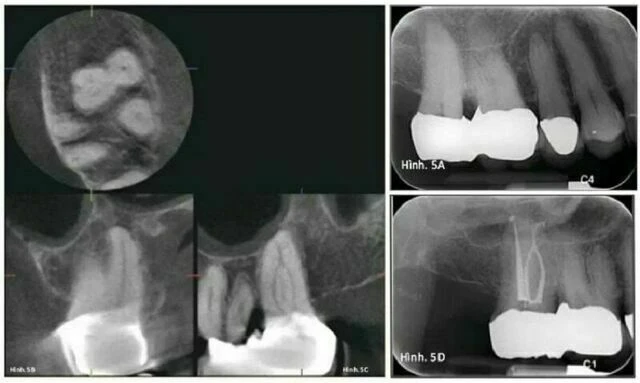

Bệnh nhân được trình bày dưới đây bị viêm tủy không hồi phục ở răng số #2, được xác nhận bởi phản ứng đau kéo dài khi thử nhiệt bằng lạnh và nóng. Chụp X quang thông thường cho thấy cấu trúc chân răng dính nhau với rất ít hoặc không có thông tin gì về giải phẫu ống tuỷ (Hình 5A).

Hình ảnh chụp CTCB bằng Accuitomo cho thấy răng cối lớn này chỉ có ba ống tuỷ (xác nhận lại một lần nữa) và hai ống tuỷ ngoài nối nhau ở một phần ba chóp và sau đó phân nhánh một lần nữa (Hình 5B & C). Chụp X quang thông thường sau điều trị cho thấy đặc điểm giải phẫu này đã được xử lý, với thông tin giải phẫu đã được thông báo trước (không tìm ống tuỷ thứ tư, biết rằng hai ống tuỷ ngoài nối với nhau ở một phần ba chóp – rất bất thường – và với thời gian thích hợp cho quá trình bơm rửa, cho phép trám bít ống tuỷ ở phần phân nhánh tại chóp sau khi nối nhau (Hình 5D).